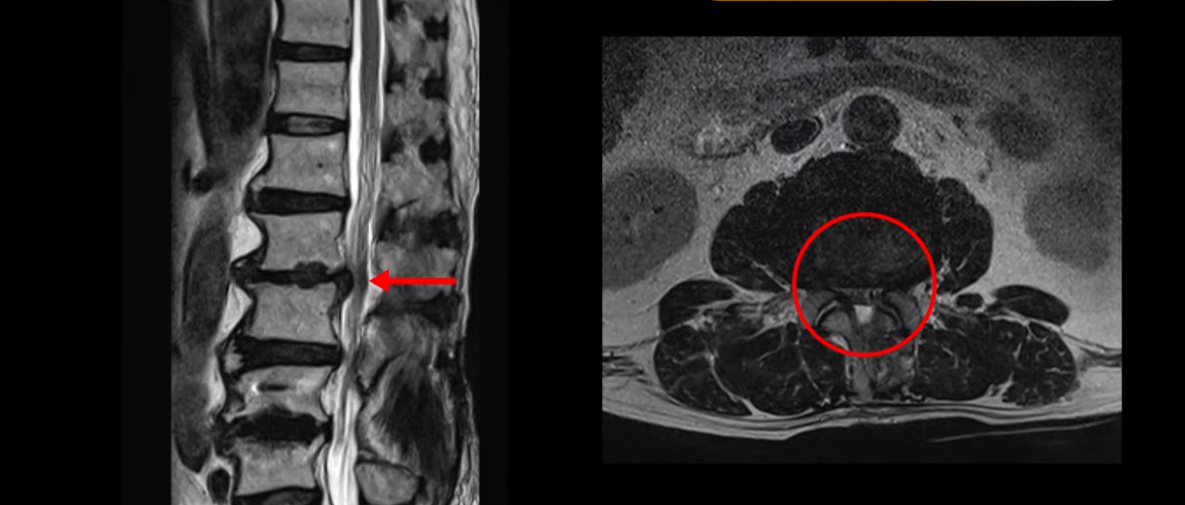

이분 허리 MRI를 보면서 간단히 설명드린 후 유합술 이후 인접마디에 문제가 생긴 환자분들이 왜 추가적인 수술을 서두르기보다는 허리기능을 살려주는 근육신경재활치료를 받는 게 좋은지, 또 치료는 어떻게 하는 게 좋은지 자세히 설명드리겠습니다. 이분 MRI를 보면 4번 5번에 나사가 박혀있습니다.

이렇게 나사가 박혀있으면 그 위나 아래에 문제가 많이 생기고 그걸 인접분절질환이라고 부릅니다. 이분도 유합술을 받은 그 윗마디인 2번 3번에서 디스크가 터져 밀려나와서 수술을 받았는데

이게 수술 후 사진인데도 여전히 척추관은 좁습니다.

나사 박은 마디 위쪽에 수술을 받았지만 수술 후에도 전혀 통증이 좋아지지 않고 다리에 힘도 빠져서 워커를 잡고 겨우 걷는 상태였습니다. 이렇게 유합술 이후 그 위나 아래에 문제가 생기는 인접분절질환은 모든 척추질환 중 가장 치료가 어려운 질환 중 하나로 꼽힙니다.